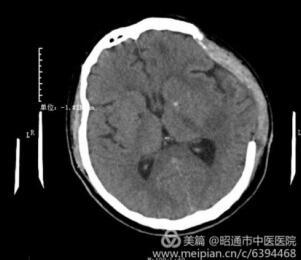

高血压性脑出血患者在我院得到有效治疗

近日,我院肿瘤科主任李庭军与刚从华西医院神经外科进修归来的住院医师凌征龙,共同完成了...